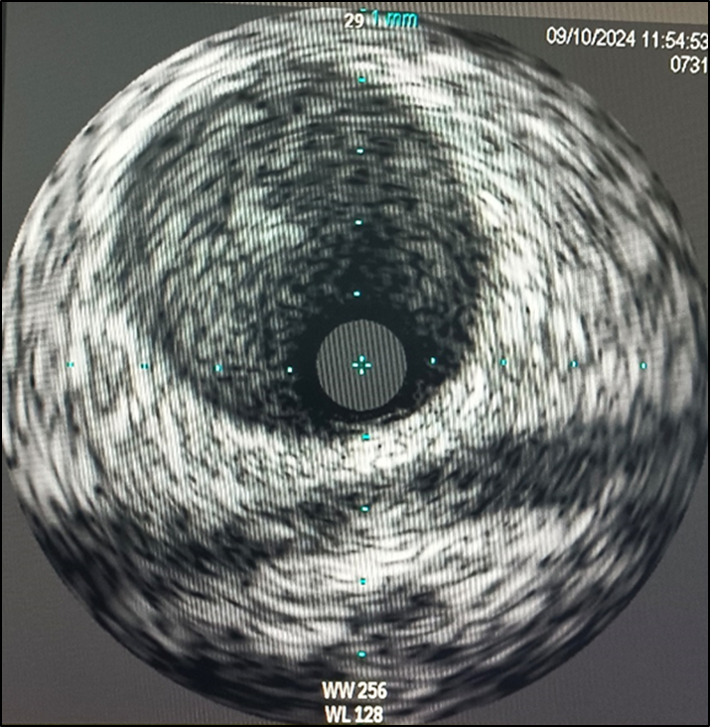

Inserted Sion wire and thrombuster to LAD revealed multiple red clots.SC balloon 2.0 x 15 mm, then 2.5 x 15 mm, was inflated at mLAD up to 12 atm. IVUS insertion to LAD revealed vessels’ size LM 5-5.5 mm, pLAD 4-4.5 mm, mLAD 3-3.5 mm with intraluminal thrombus, dLAD 2.75-3 mm. Multiple inflations were done at mLAD with SC balloon 2.5 x 15 mm. After multiple SC balloon inflations, the CAG revealed slow flow phenomenon. Then, the operator performed thrombus aspiration, multiple SC balloon 2.0 x 15 mm inflation and gave IC integrillin 3.4 ml. The final angiogram was acceptable result. The anticoagulant was given after CAG. Chest pain was subsided and hemodynamic parameters remained stable. EKG recorded after angiography showed resolution of ST elevation at V1-3. Later, the patient was discharged with warfarin. The Aortomitral intervalvular fibrosa repair surgery was planned due to embolic complication.

Case Summary